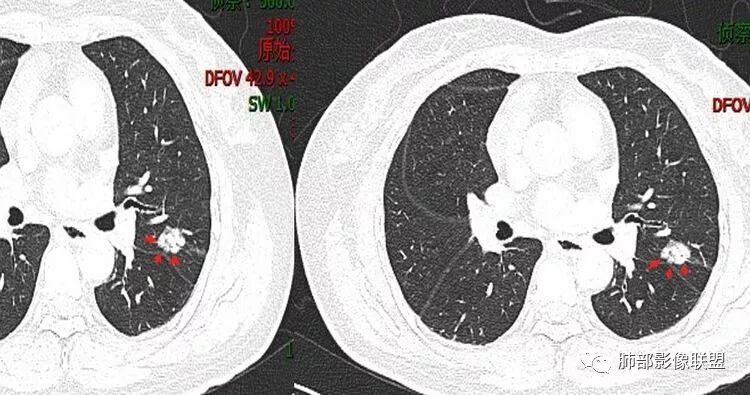

脐凹、分叶

看看这个。左边为什么会胸膜往上?因为左边是GGO为主,右边是比较实,就占位效应出来,所以凸出来了心灵鸡汤:@岳微-辽宁省朝阳234医院-影像诊断 应该是心包隐窝初学者:如是炎症,是同步发生,首先边缘不会有边界清楚的GGO,慢性炎症应该连渗出都很少了,更加不会有一部分是收缩,一部分是膨隆

南边:有边界清楚GGO吗张玉:有南边:有就好办边界清楚MGGO,分叶、胸膜凹陷

下面这个如何考虑?

wonderful:

那么小不转移吧,另外一个结节?

初学者:

不是转移。毛玻璃,原发可能,需要随访

南边:

边界清GGO?随访是个好主意

天涯:

会不会是肺内淋巴结?

一般临床处理是立刻开左边的,在胸膜旁的很好定位。右边随访

肺内淋巴结是实性的

淋巴结一般实性